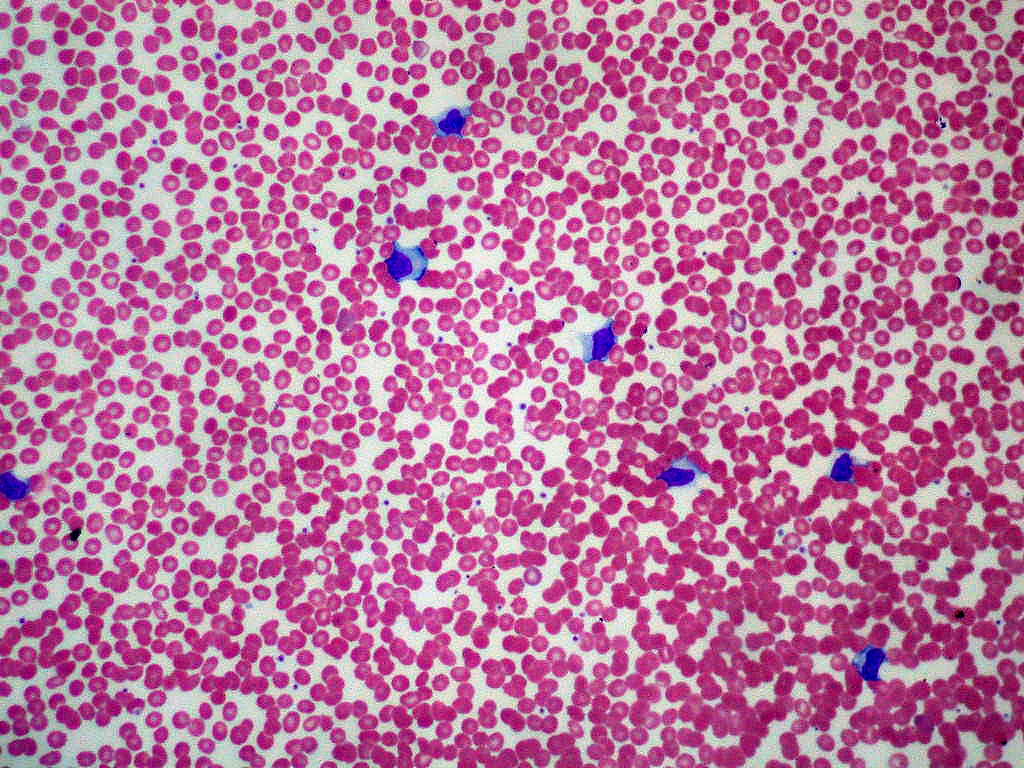

Parenting La mononucleosi è un'infezione virale che si può contrarre anche in gravidanza. Quali sono i rischi per mamma e bambino se contratta?